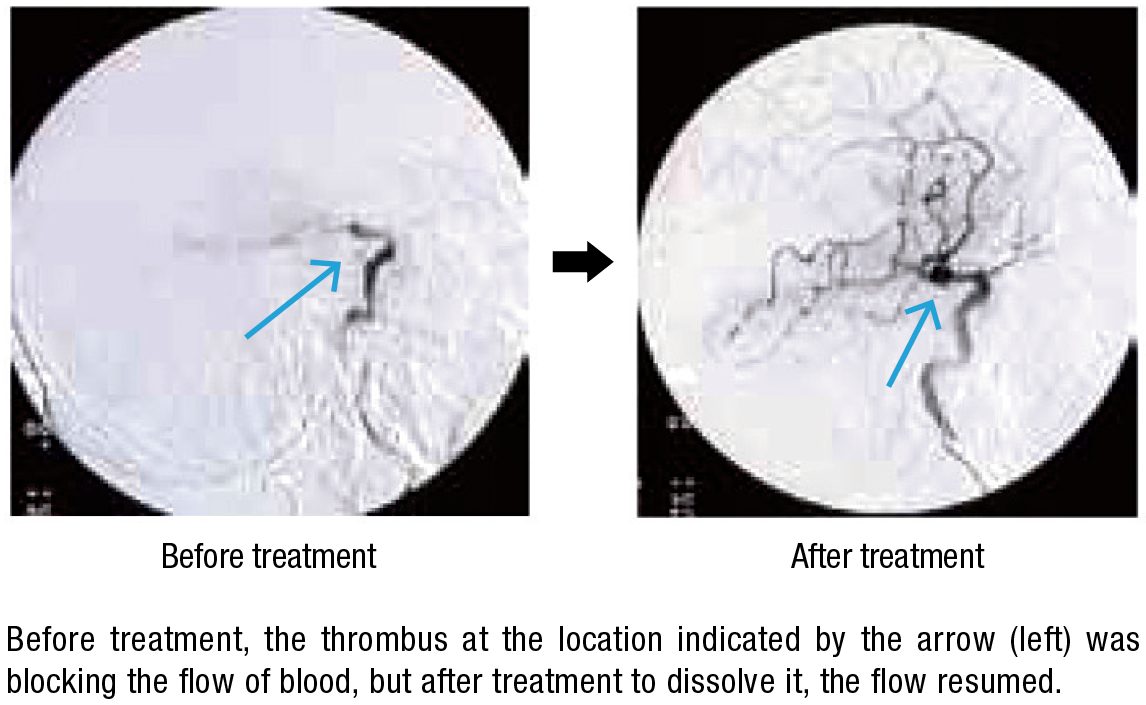

Hamamatsu Photonics has also developed many world-class products in the field of lasers, in which it started R&D activities in the 1990s. Recently it became the first in the world to develop a laser thrombolysis technology for treatment of cerebral thrombi—blood clots in the brain that cause strokes—which works as follows: A catheter encasing an optical fiber is inserted via a femoral artery and extended to the location of the thrombus, and a green laser beam at a wavelength of 532 nanometers is directed at the site. At this wavelength, the beam is not absorbed by the blood vessel wall but affects only the thrombus, which it dissolves with almost no risk of damage to the blood vessel walls. Since the tip of the catheter is thin, with a diameter of only 0.8 millimeters, and flexible, it can be used for treatment in blood vessels of around 1 mm in diameter, which are hard to treat with existing devices for suction-purpose catheterization. In this way it offers hopes for expanding the scope of cases that can be treated.

Hamamatsu Photonics has been conducting its research in collaboration with a local hospital and Hamamatsu University School of Medicine. Dr. Hiroyuki Okada, who is responsible for laser thrombolysis R&D at the company’s Central Research Laboratory, explains, “We had a hard time reconciling the different mind-sets of the medical treatment staff and the engineers.” The engineers wanted to create a device allowing fine-tuning of irradiation times, power, and other settings, while the medical staff wanted a simple-to-operate device that would let them concentrate on treatment. He says, “We put the wishes of the medical staff first and made adjustments, such as minimizing the number of operating buttons, while aiming for high reliability.” The effectiveness and safety of laser thrombolysis technology has been confirmed in experiments on animals, and it is planned to start clinical tests on humans this spring; the aim is to create a product for practical use in five years.